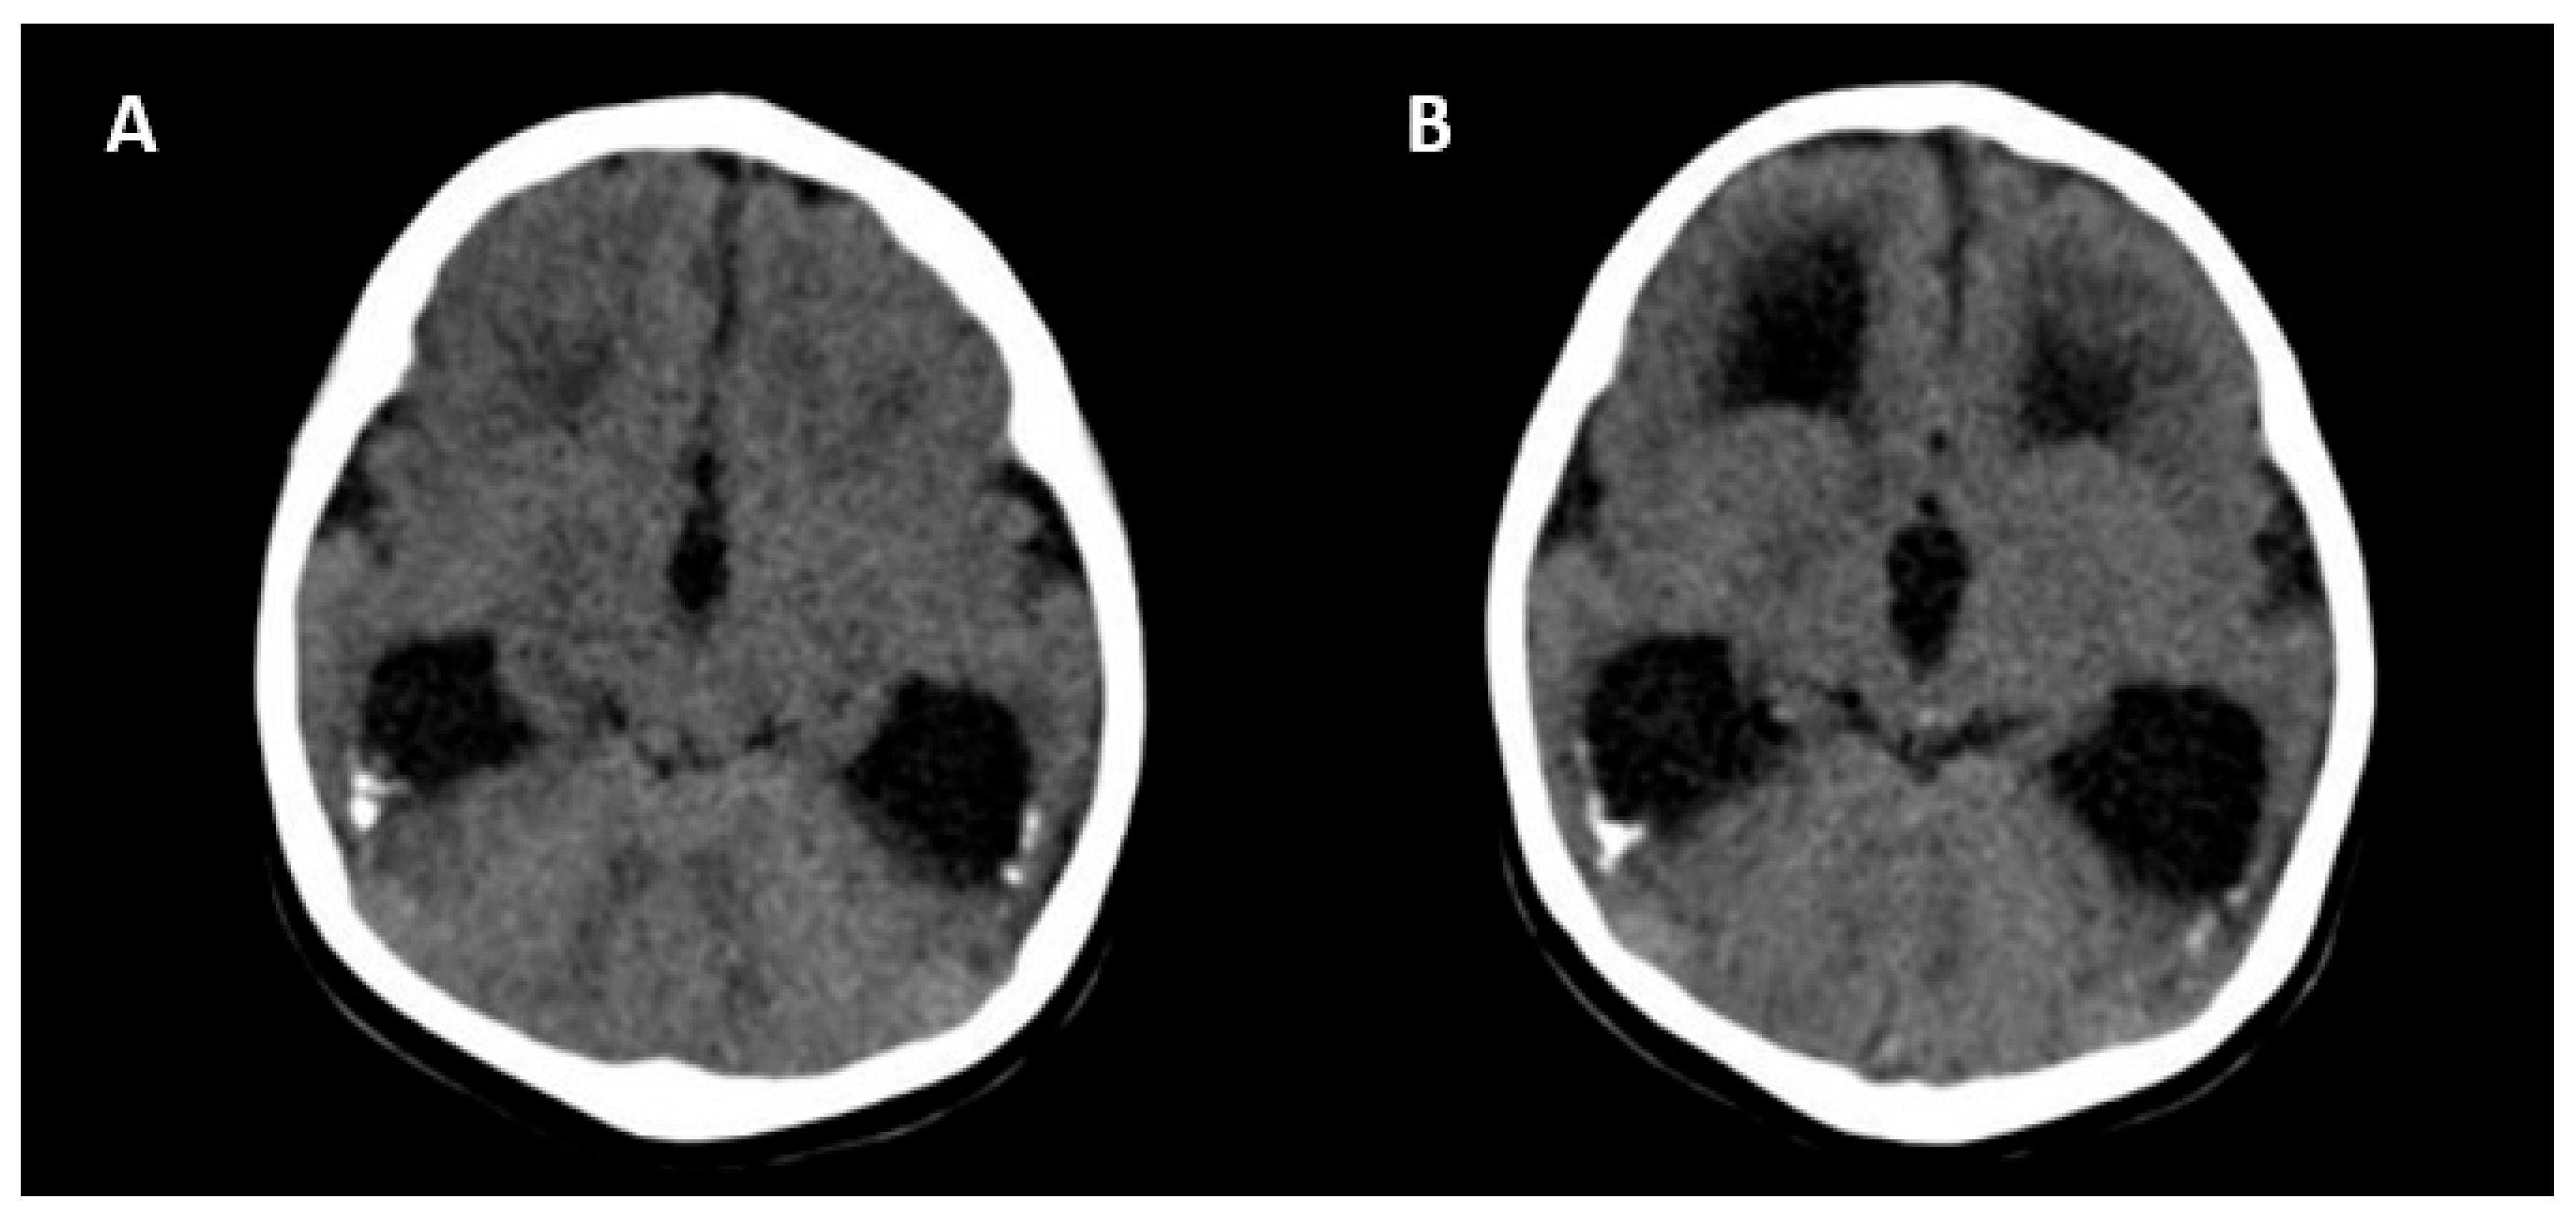

The absence of CNS abnormalities on ultrasound and MRI is associated with a good prognosis [25]. Unfavorable outcomes include the following: neurological symptoms (tetraplegia/cerebral palsy, lethargy and/or hypotonia, chorioretinitis, sensorineural hearing loss, microcephaly and delayed neuropsychomotor development), abnormal CNS imaging findings at birth, hematological alterations (thrombocytopenia/liver enzymes), and termination of pregnancy due to fetal malformations [25]. Figure 5 shows the CNS abnormalities using computed tomography in a newborn with intrauterine CMV infection.

Figure 5.

Computed tomography axial view of a newborn skull with intrauterine cytomegalovirus infection showing periventricular calcifications (A) and moderate ventriculomegaly (B).